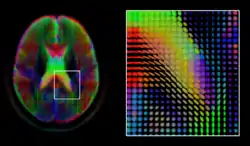

A mid-axial slice of the ICBM diffusion tensor image template. Each voxel's value is a tensor represented here by an ellipsoid. Color denotes principal orientation: red = left-right, blue=inferior-superior, green = posterior-anterior

Diffusion MRI is a structural magnetic resonance imaging modality that allows measurement of the diffusion process of molecules. Diffusion is measured by applying a gradient pulse to a magnetic field along a particular direction. In a typical acquisition, a set of uniformly distributed gradient directions is used to create a set of diffusion weighted volumes. In addition, an unweighted volume is acquired under the same magnetic field without application of a gradient pulse. As each acquisition is associated with multiple volumes, diffusion MRI has created a variety of unique challenges in medical image computing.

The diffusion tensor,[58] a 3 × 3 symmetric positive-definite matrix, offers a straightforward solution to both of these goals. It is proportional to the covariance matrix of a Normally distributed local diffusion profile and, thus, the dominant eigenvector of this matrix is the principal direction of local diffusion. Due to the simplicity of this model, a maximum likelihood estimate of the diffusion tensor can be found by simply solving a system of linear equations at each location independently. However, as the volume is assumed to contain contiguous tissue fibers, it may be preferable to estimate the volume of diffusion tensors in its entirety by imposing regularity conditions on the underlying field of tensors.[59] Scalar values can be extracted from the diffusion tensor, such as the fractional anisotropy, mean, axial and radial diffusivities, which indirectly measure tissue properties such as the dysmyelination of axonal fibers [60] or the presence of edema.[61] Standard scalar image computing methods, such as registration and segmentation, can be applied directly to volumes of such scalar values. However, to fully exploit the information in the diffusion tensor, these methods have been adapted to account for tensor valued volumes when performing registration [62][63] and segmentation.[64][65]